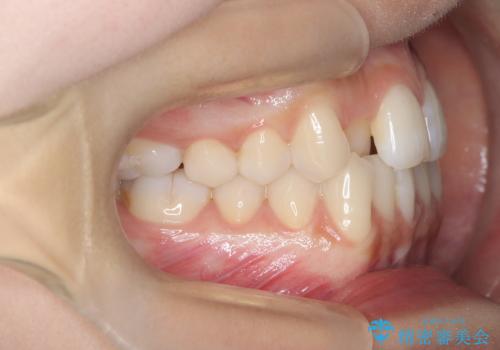

1年でここまで変わる。デコボコ歯並びの非抜歯矯正!

- 歯のデコボコ(叢生)を主訴にご来院された患者様です。

精密矯正検査を行った結果、歯を抜かずに行う、非抜歯のワイヤー矯正で治療を行う方針となりました。

歯並びの乱れに加え、**反対咬合(上下のかみ合わせのズレ)**も認められたため、見た目だけでなく、かみ合わせの改善も同時に行っています。

治療後は歯並び・かみ合わせともに大きく改善し、患者様にも大変ご満足いただけました。